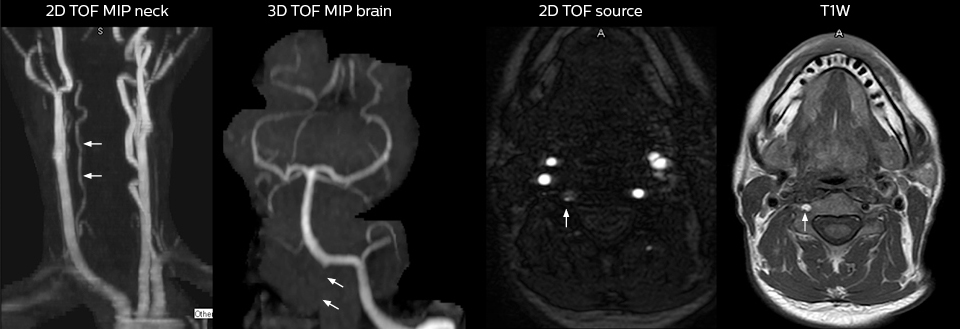

Cervical spine routine exam

This patient presented with headache that was worse with neck flexion and we see a Chiari 1 malformation with low-lying cerebellar tonsils as well as some degenerative cervical thrombolytic change.